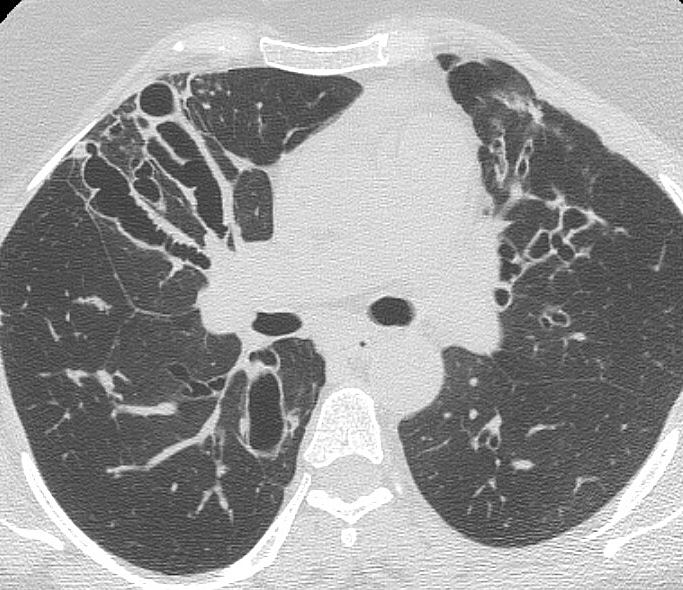

Bronchiectasis

Case 8 CT1